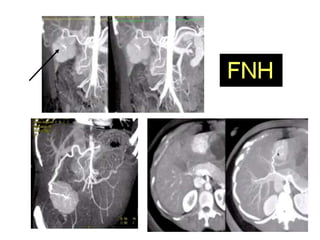

FNH

Predomina en mujeres.

Menos del 20% de los pacientes son

sintomáticos.

No tienen potencial maligno.

Se considera actualmente que es una

respuesta del parénquima hepático a una

malformación vascular preexistente.